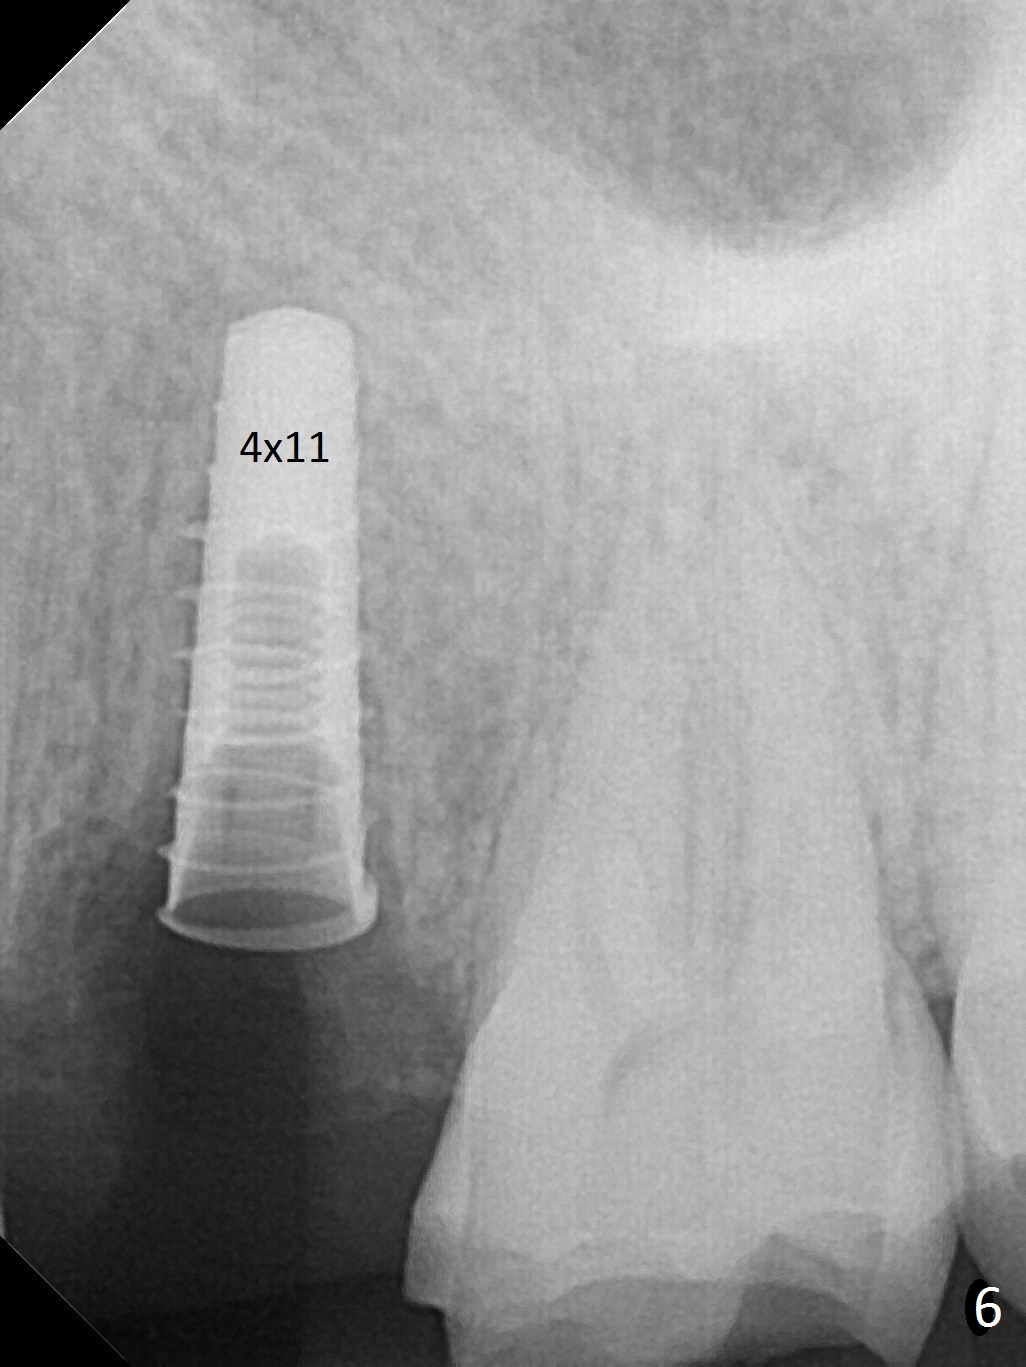

The buccal gingiva over the tooth #13 (Fig.1 white *) with crack (Fig.2 (mesial view of the extracted tooth)) is erythematous with deep buccal (B) pockets, which do not appear to extend the level of exostosis of the neighboring teeth (Fig.1 black *), i.e., coronal to the apical end of the crack with granulation tissue (Fig.2 *). Osteotomy is initiated with a 1.6 mm drill in the palatal aspect of the socket (Fig.3) so that an implant will be placed palatal (Fig.8,11) and there is enough buccal gap for bone graft (Fig.8 *). After withdrawal of 3.3 mm Magic Drill (trephine bur), the osteotomy (Fig.4 O) plug (red outline) is intentionally left in situ. When a 4x11 mm dummy implant is placed (Fig.5 (green outline), 6), the plug is compressed (Fig.5). With placement of a definitive implant (4.5x13 mm, Fig.7 (green), 9), the plug as well as the sinus floor (Fig.4 SF) is lifted (Fig.7 red curved line), 9 (arrowheads)). In brief the autogenous bone is used for sinus lift. There is no intra- or post-op nasal hemorrhage. With a small piece of gauze (Fig.8 G) in the implant well, allograft is placed in the buccal (mainly) and palatal gaps until the level of the implant plateau. Then a 4.5x4(3) mm abutment is placed (Fig.9-10 A). Next another piece of gauze is placed in the space corresponding to the abutment cuff (Fig.11 G) for fabrication of an immediate provisional (Fig.12 P). More bone graft is placed in the soft tissue zone (dual zone technique) after gauze removal and before provisional seating. With dual zone bone graft technique and provisional support, the soft tissue atrophy should be expected to be minimal (Fig.12 *). The zone of exostosis (more coronal) should be much less, since the bone density in the zone is high.